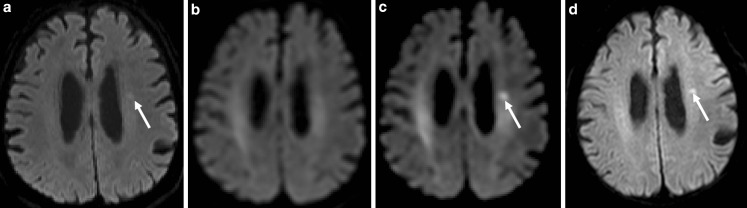

An 87-year-old man presented with dysarthric speech for 1 day and underwent magnetic resonance imaging (MRI) using a 3-Tesla MRI scanner. Diffusion-weighted imaging (DWI) using a b-value of 1000 s/mm2 showed a small abnormality with high intensity on the left side of the deep white matter (Fig. 1a). The DWI using a b-value of 1500 s/mm2 and different diffusion times showed that the infarction was obscured in some images (Fig. 1b) and clear in others (Fig. 1c). The effective diffusion time was 8.5 ms for the image shown in Fig. 1b and 47.3 ms for the image shown in Fig. 1c. The infarction was shown clearly in DWI and T2-weighted images obtained during an MRI examination that was completed 2 days after the initial examination (Fig. 1d).

Diffusion-weighted imaging of the brain of the 87-year-old patient showing the acute infarction (arrow). a DWI (b-value = 1000 s/mm2, diffusion time = 22.3 ms), b DWI (b-value = 1500 s/mm2, diffusion time = 8.5 ms), c DWI (b-value = 1500 s/mm2, diffusion time = 47.3 ms), d DWI (b-value = 1000 s/mm2, diffusion time = 22.3 ms) obtained 2 days after the image in Fig. 1a

Recent advances in MRI have allowed a reduction in echo time, which has theoretically led to improvement in DWI quality; however, the diffusion time of DWI decreases with the reduction of echo time. Therefore, the utility of this method might be changed, making it inappropriate for the detection of a lesion with restricted water diffusion, such as an acute cerebral infarction. A short diffusion time leads to dramatically reduced diffusion contrast in images of stroke in humans [1]. In the present case, the echo time and diffusion time for the image shown in Fig. 1a are 60 ms and 22.3 ms, respectively. The diffusion time may not be sufficient for the detection of acute cerebral infarction, as in this case.

Previous reports have shown the utility of high b‑value DWI to detect acute ischemic stroke [2, 3]: however, the b‑value itself is not an important factor. As the b‑value used for DWI increases, the diffusion time naturally becomes longer due to hardware limitations of clinical MRI systems. In the presented case, the image shown in Fig. 1b was obtained using a higher b‑value than that shown in Fig. 1a, but the lesion is less clearly demonstrated due to the shorter diffusion time. It should be noted that diffusion time is the key factor for enhancing contrast in DWI.